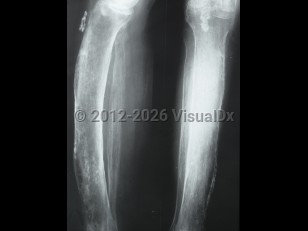

PeriostitisPeriostitis